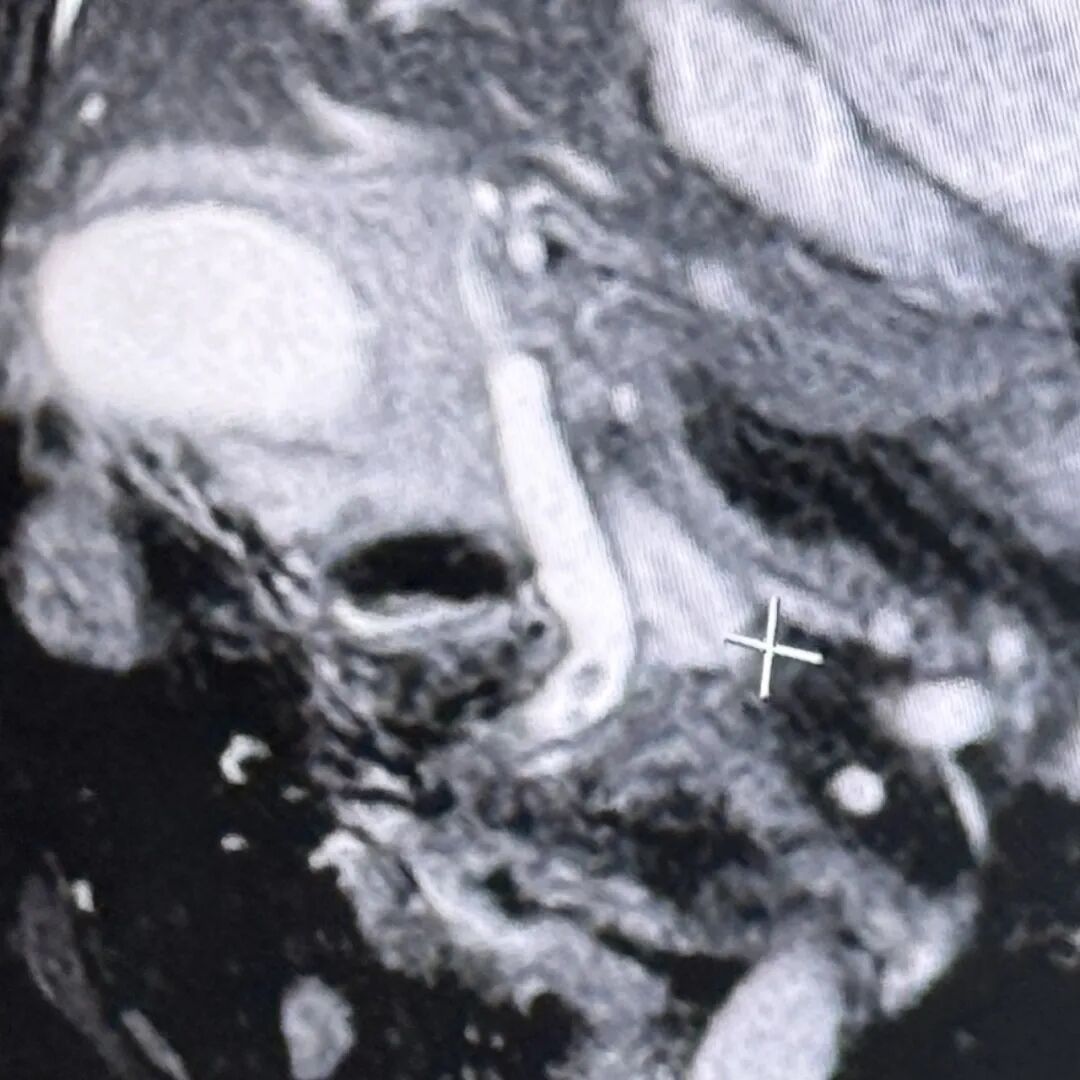

经过全面评估,团队最终决定实施ERCP+EST+ENBD+LC术,这是一种微创手术组合方案,通过内镜逆行胰胆管造影(ERCP)及相关技术取出胆总管结石,再行腹腔镜胆囊切除术(LC)切除病变胆囊。该方案避免了传统开腹手术的大创伤,更适合高龄、基础疾病多的患者。

手术由盛成胜主任团队开展,先将内镜经口腔插入至十二指肠降段,找到胆管开口后,行十二指肠乳头括约肌切开后,取出胆总管内的结石,最后置入鼻胆管引流。

随后进行腹腔镜胆囊切除术,术中见大网膜粘连包裹胆囊,胆囊已化脓坏疽,大小约12cm×8cm×6cm,手术团队仔细钝性分离粘连,小心避开周围组织血管,完整切除了病变胆囊。